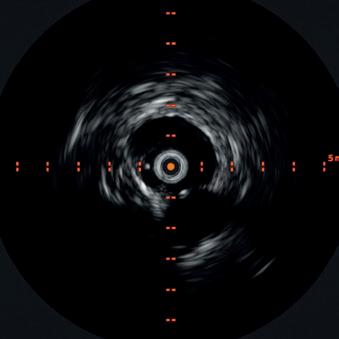

Endovascular interventions for chronic limb-threatening ischemia (CLTI) are technically demanding endeavors. Multi-level arterial disease, long-length lesions and other complex plaque characteristics are frequently encountered when treating these patients.1,2 Calcium modification with intravascular lithotripsy (IVL) has emerged as a useful tool to combat the challenges of calcified lesions with the goal of maximizing luminal gain to achieve improved endovascular outcomes, both radiographically and clinically.3 Balanced lithotripsy pulse delivery across longer-length lesions, as well as effectively treating calcified disease across multiple arterial beds, can be laborious considering the number of available pulses and the length of the IVL catheter relative to the extent of disease.

An arteriogram of the left lower extremity was performed via antegrade left common femoral artery access based on preoperative review of the lower extremity arteriogram from Uzbekistan. Scattered non-calcified plaque with moderate to high-grade stenoses were identified in the proximal and mid superficial femoral artery. Diffuse severe calcified tibial artery disease was identified. There was a long segment stenosis of the proximal and mid posterior tibial artery coupled with a more distal occlusion. The proximal peroneal artery was calcified and occluded with distal reconstitution identified. There was complete occlusion of the anterior tibial artery (Figure 2).